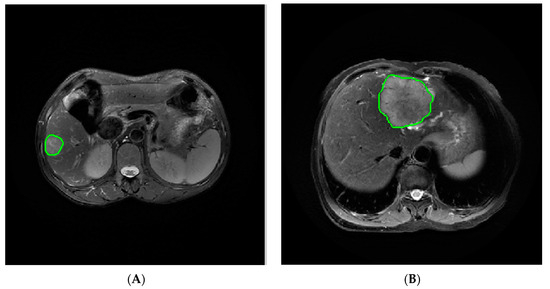

2.3. Image Segmentation and Feature Extraction